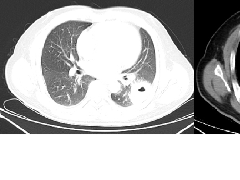

实变是OP病例中最常见的发现,发生在近75%的病例中,病变通常在双基底、支气管血管周围和/或外周(图2,3)。实变可以发生在肺的任何部位,边界清晰或模糊,呈游走性的特点(图4,5),可以呈局灶性,多发性和弥漫性,也可以表现为结节或肿块(图6)。实变常伴支气管充气征,可伴散在的磨玻璃样低密度或小实质结节。以主要的或完全的磨玻璃低密度为表现的较少见(图7)。磨玻璃低密度合并小叶间隔增厚可表现为铺路征(图8)。

范围从小的微结节(<4mm)(图9)到较大的离散结节(通常达1cm),以及较大的结节或肿块(图10)。后者常被描述为具有不规则或锐利边缘,通常包含支气管充气征(图11)。结节可以单发或多发,通常为实性结节或部分实性结节(图12)。虽然PET扫描对这些病变的评估显示标准化摄取值轻微升高,但结果是非特异性的,临床价值有限(图13、14)。不常见的OP类型为小结节型,包括弥漫性小叶中心型模糊结节(如在非纤维性过敏性肺炎[HP]病例中可见)和树芽征,提示细支气管感染和/或炎症。

这种类型包括表现为线状不透明的实质条带,通常延伸到胸膜表面,通常先于磨玻璃样或实变(图15)。其他表现包括小叶周围增厚和具有反晕外观特征的病变(图16)。这个标志,也被称为“环礁征”,其特征是中央磨玻璃不透明(GGO)和外围实变。这些成像模式有着惊人相似的特征,通常可以在相同的情况下识别,甚至在同一张图像上。OP和慢性嗜酸性粒细胞性肺炎之间有相当多的共通之处,特别是当病变主要分布在上叶时。